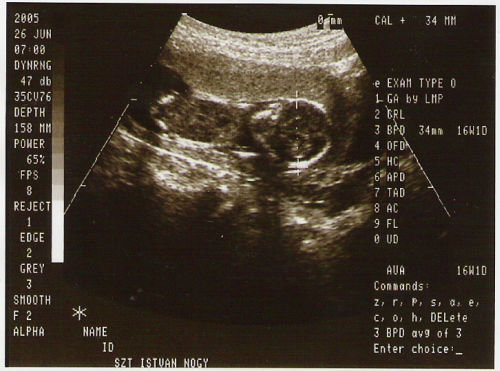

Itt vagyok! Dávid elaludt,reggel korán kelt,mert mentem a korházba Afp-re.

Sajnálom,hogy nem jött össze az uh.

pedig nagyon szorítottam.